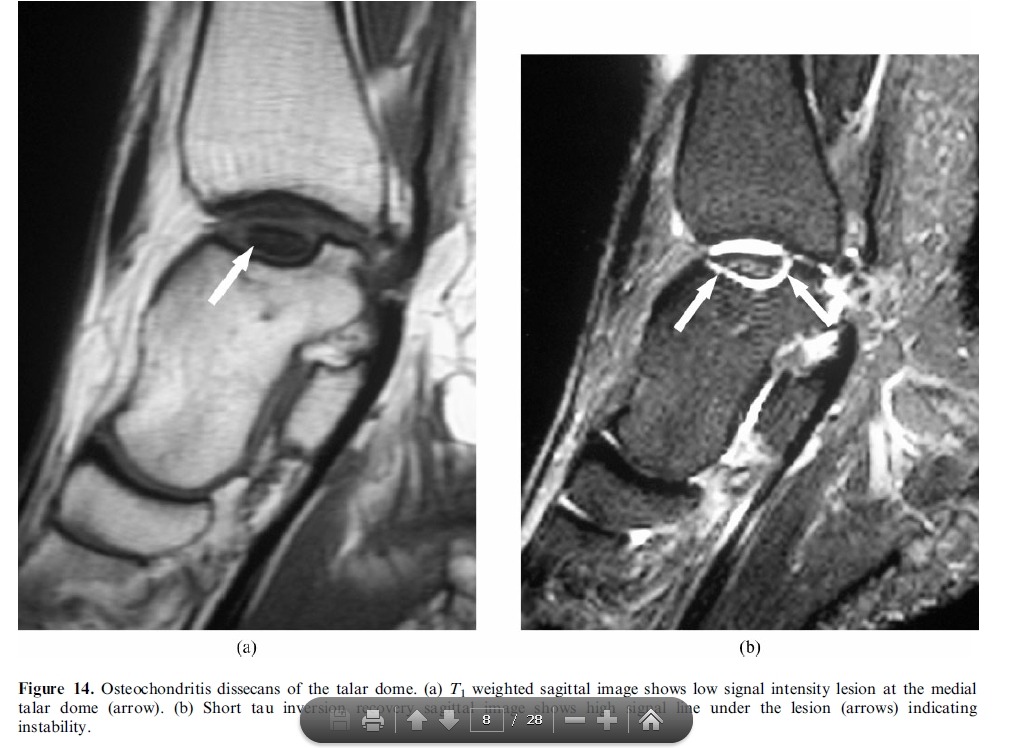

Trevor’s disease